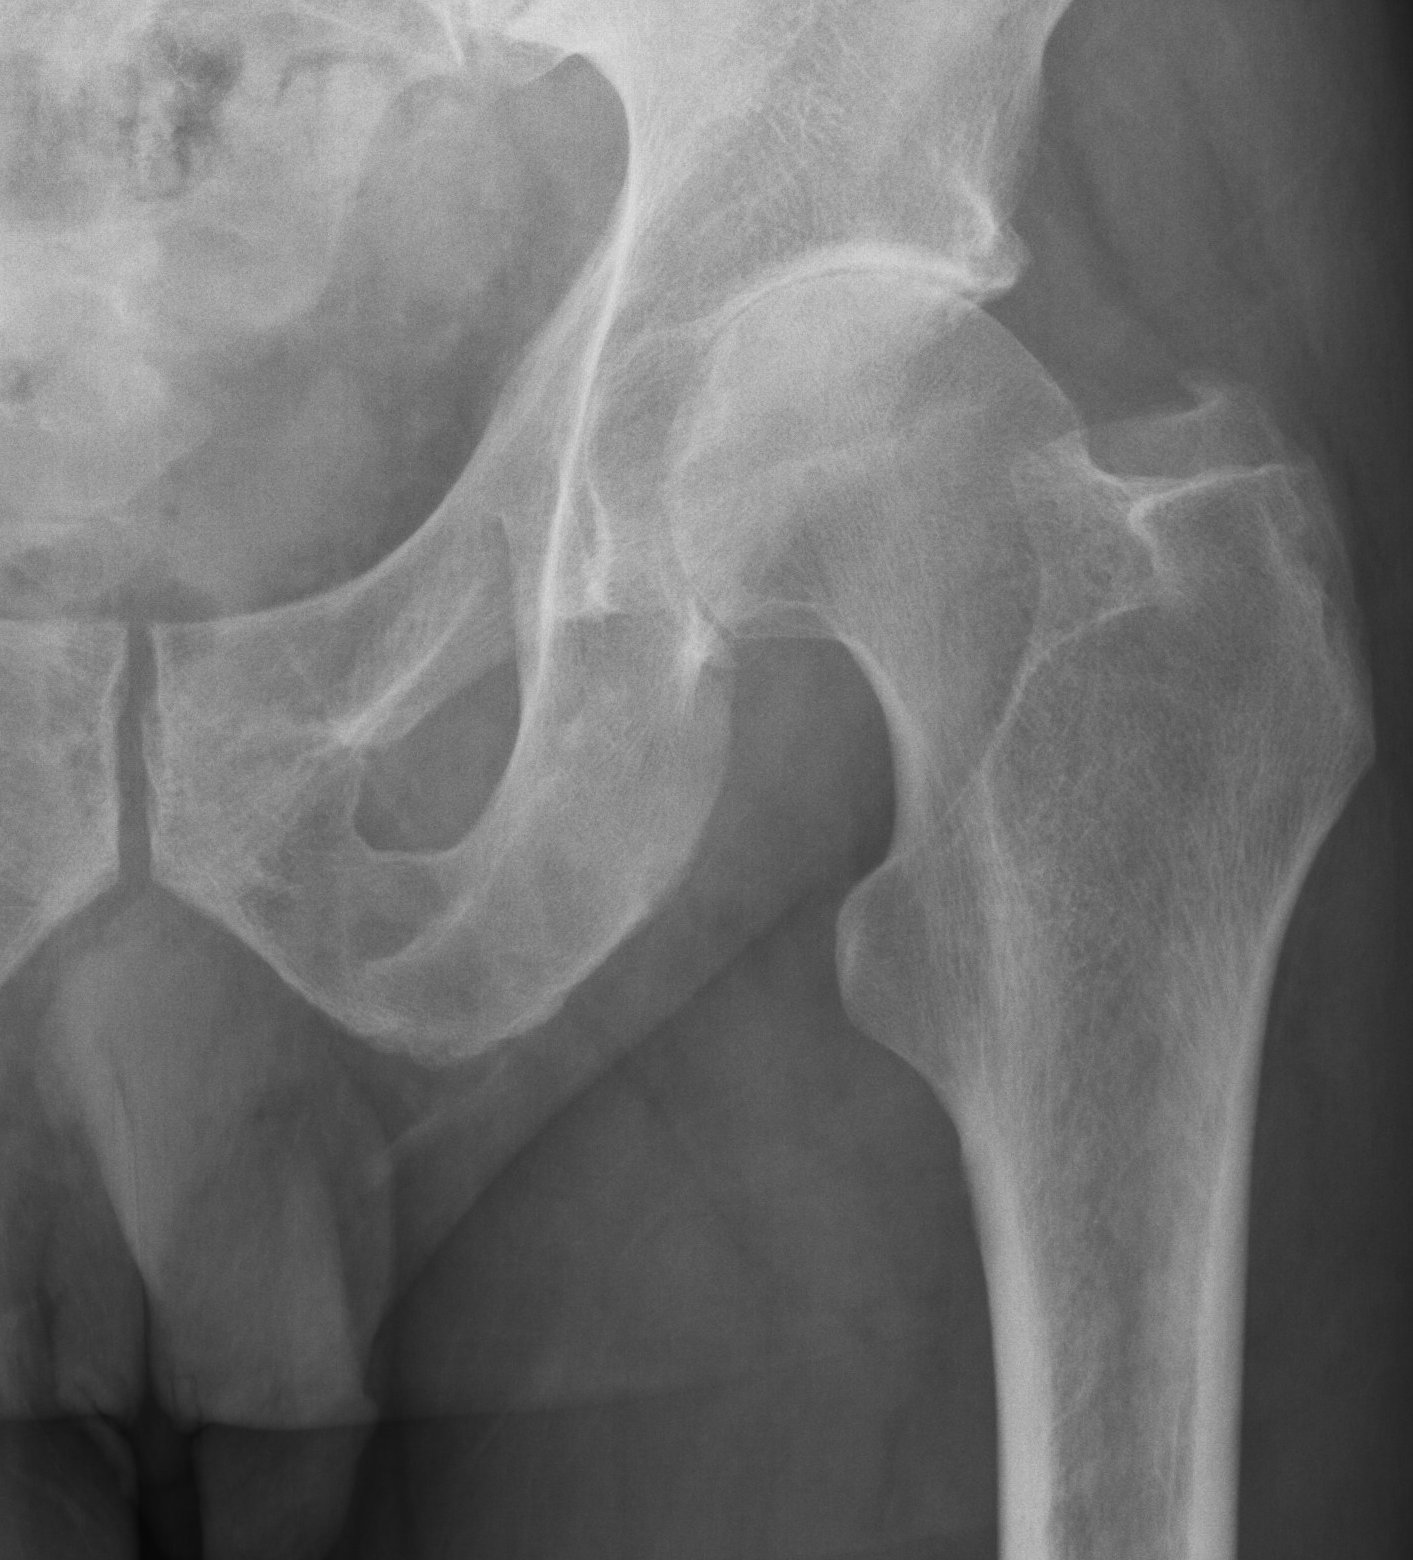

Patients usually present with a very rapid onset of severe pain and signs of toxicity. In patients who are very immuno-compromised there may not be the usual signs of systemic reaction to infection. In the early stages x-rays may mimic arthritis or AVN.

MRI is very sensitive but may still struggle to differentiate between advanced sepsis and AVN.

Aspiration of the hip joint, with x-ray control is the diagnostic test of choice. Staphylococcus aureus continues to be the most common organism isolated from adult hips affected by sepsis. Rarely, spontaneous nongonococcal and Candida sepsis of the hip joint in otherwise healthy adults have been reported. Gonococcal septic hip arthritis is less common, and it is usually associated with specific host risk factors.